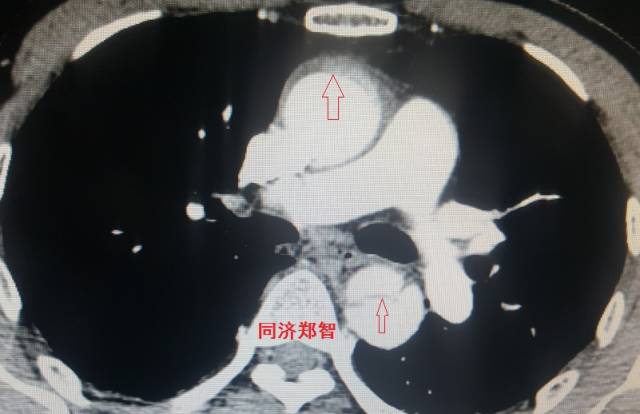

病例七

平扫CT提示升主动脉及降主动脉内膜片,CTA证实为A型主动脉壁间血肿。

图14-15